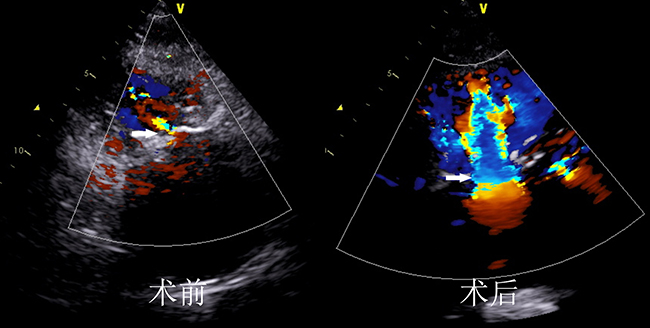

微创手术前后的B超图片对比

7月26日,张明奎带领团队为患者实施了“经导管三尖瓣植入手术”,随着新植入瓣膜的顺利打开,患者血压很快上升,氧饱和度立即恢复到正常,食道超声监测新植入瓣膜启闭良好,没有狭窄和瓣周漏,同时观察到术前开放的卵圆孔分流消失,手术完全成功,日前患者已经康复出院。